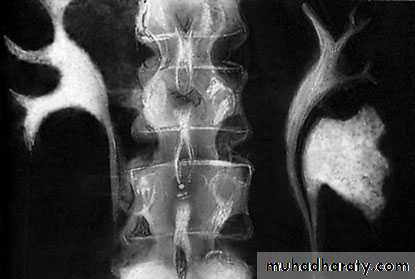

Horseshoe Kidney

found in 1:1000 necropsies an is commoner in men.

probably the most common of all renal fusion anomalies

The anomaly consists of two distinct renal masses lying

vertically on either side of the midline and connected at

their respective lower poles by a parenchymatous or fibrous

isthmus that crosses the midplane of the body.

Fusion of the renal masses early in embryonic life, so its ascent

will be impeded by inferior mesenteric artery.

The kidneys are low located, mal rotated and pelves lie anteriorly

Symptom When present, they are related to complications like hydronephrosis, infection, or calculus formation

Diagnosis ultrasound, IVU, CT scan